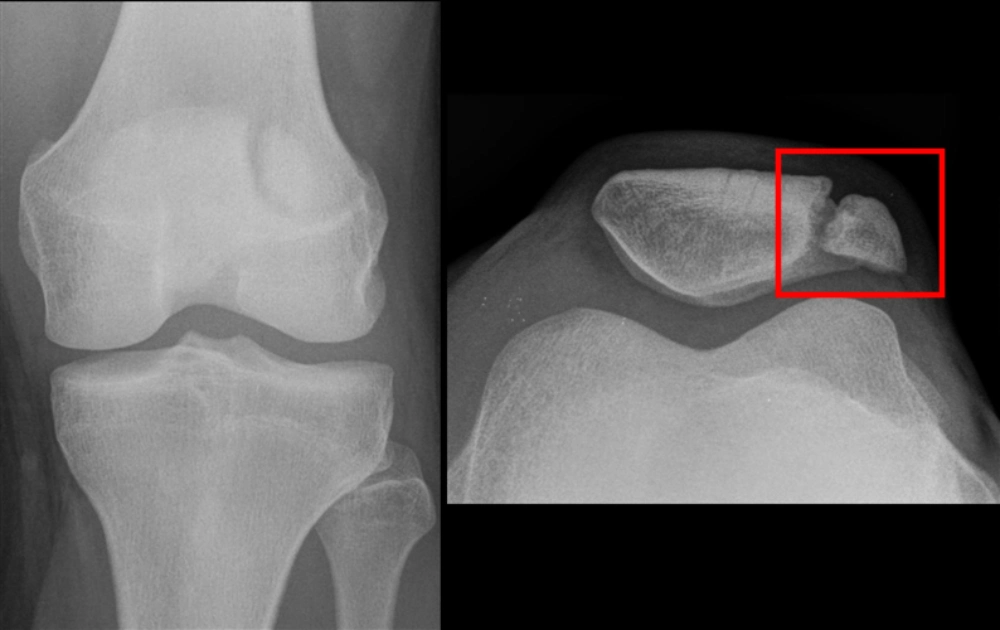

عمل پی آر پی زانو؛ روشی کمخطر برای درمان زانودرد

تزریق پی آر پی (PRP) یک روش غیرجراحی نوین برای درمان مشکلات زانو است. پی آر پی نوعی پلاسمای غنی از پلاکت است که از خون بیمار گرفته میشود. از آنجایی که غلظت فاکتورهای رشد در پی آر پی بالا است، زمانی که این مایع به زانو تزریق میشود، مواد ضروری برای بازسازی بافت آسیبدیده […]